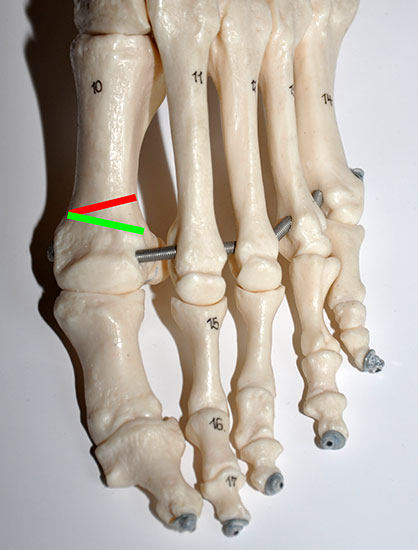

Eine Hallux valgus Fehlstellung besteht typischerweise aus einem erhöhten Intermetatarsale I/II Winkel, einer Adduktion und ggf. Pronation der Großzehe, sowie häufig aus einer Valgusstellung innerhalb der Großzehe (Hallux valgus interphalangeus). Wie bei der klassischen Chevron-Osteotomie erfolgt die Korrektur des erhöhten Intermetatarsalwinkel I/II durch eine Lateralverschiebung des Metatarsale I Kopfes. Ein laterales Release wird transartikulär von dorsal über eine Stichinzision lateral der Strecksehnen durchgeführt.

Die Korrektur eines erhöhten Interphalangealwinkels läßt sich durch eine mediale, schließende Osteotomie der Grundphalanx erreichen (Akin). Die Osteotomieebenen und die Fixation orientieren sich an den offenen Verfahren.

Durch die Korrektur extraartikulär im Schaftbereich lassen sich auch große Intermetatarsalwinkel korrigieren.